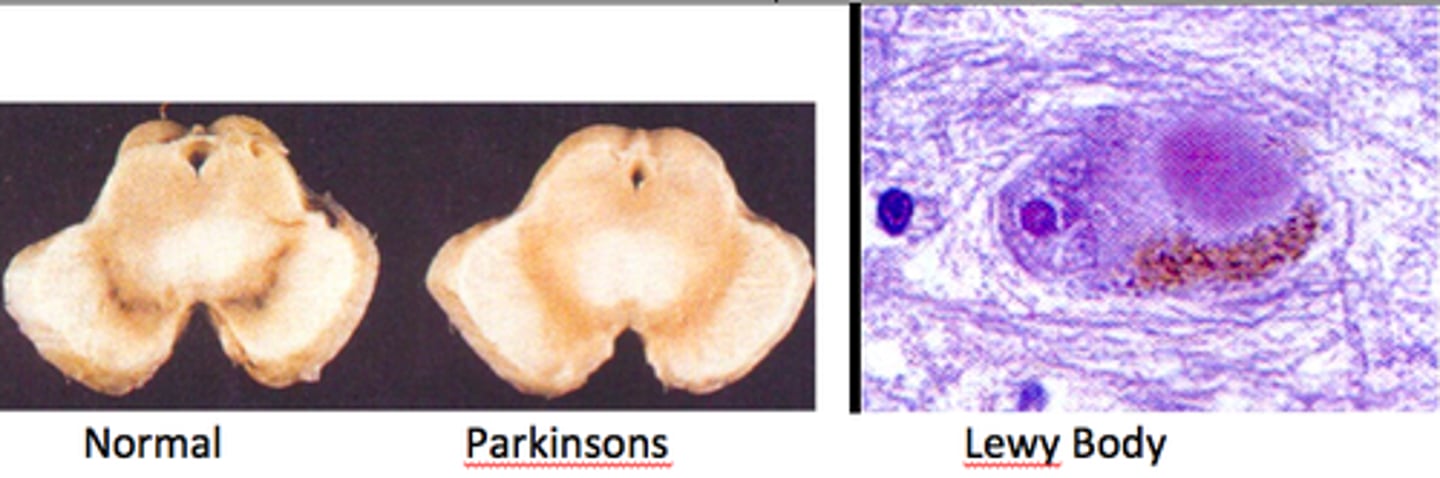

Resting tremor, rigidity, akinesia, postural instability, shuffling gait

Parkinson disease (loss of dopaminergic neurons in substantia nigra pars compacta)